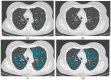

Chronic obstructive pulmonary disease (COPD) is one of the leading causes of death. Recent studies have underlined the importance of non-contrast-enhanced chest CT scans not only for emphysema progression quantification, but for correlation with clinical outcomes as well. As about 40 percent of the 300 million CT scans per year are contrast-enhanced, no proper emphysema quantification is available in a one-stop-shop approach for patients with known or newly diagnosed COPD. Since the introduction of spectral imaging (e.g., dual-energy CT scanners), it has been possible to create virtual non-contrast-enhanced images (VNC) from contrast-enhanced images, making it theoretically possible to offer proper COPD imaging despite contrast enhancing. This study is aimed towards investigating whether these VNC images are comparable to true non-contrast-enhanced images (TNC), thereby reducing the radiation exposure of patients and usage of resources in hospitals. In total, 100 COPD patients with two scans, one with (VNC) and one without contrast media (TNC), within 8 weeks or less obtained by a spectral CT using dual-layer technology, were included in this retrospective study. TNC and VNC were compared according to their voxel-density histograms. While the comparison showed significant differences in the low attenuated volumes (LAVs) of TNC and VNC regarding the emphysema threshold of -950 Houndsfield Units (HU), the 15th and 10th percentiles of the LAVs used as a proxy for pre-emphysema were comparable. Upon further investigation, the threshold-based LAVs (-950 HU) of TNC and VNC were comparable in patients with a water equivalent diameter (DW) below 270 mm. The study concludes that VNC imaging may be a viable option for assessing emphysema progression in COPD patients, particularly those with a normal body mass index (BMI). Further, pre-emphysema was generally comparable between TNC and VNC. This approach could potentially reduce radiation exposure and hospital resources by making additional TNC scans obsolete.